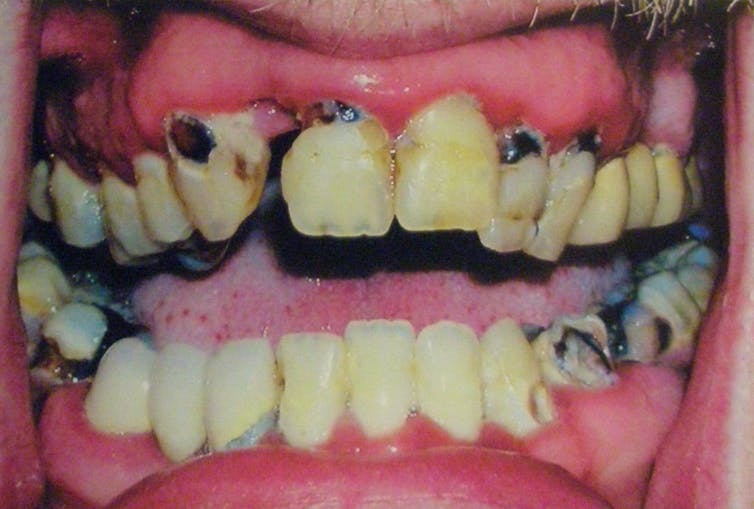

And let’s not forget “meth mouth”, the abnormal loss of teeth and accelerated tooth decay:

Sympathetic stimulation causes all sorts of secretion to stop (drugs which mimic noradrenaline are in our cold and flu medicines to stop runny noses), including saliva secretion.

This results in an increased risk of tooth decay that, combined with behavioural problems (meth addicts, we might assume, don’t prioritise brushing their teeth) and poor eating habits, means teeth are rapidly lost.